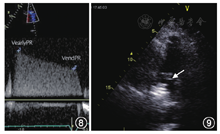

(2)根据肺动脉瓣反流压差估测肺动脉舒张压(DPAP)和平均压(MPAP)。舒张早期跨瓣压差估测肺动脉平均压;舒张晚期跨瓣压差估测肺动脉舒张末压,见图8。

注:VearlyPR舒张早期肺动脉瓣反流速度;VendPR舒张末期肺动脉瓣反流速度;RAP右心房压;DPAP肺动脉舒张压;MPAP肺动脉平均舒张压;MPAP=4(VearlyPR)2+RAP,DPAP=4(VendPR)2+RAP

(3)诊断和评估肺栓塞的重要切面之一,见图9。